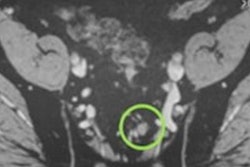

Axial Ga-68 PSMA-fused PET/MR image shows abnormal radiotracer uptake (arrow) within rounded right mesorectal lymph node. Transrectal biopsy findings were negative for malignancy. Patient underwent androgen deprivation therapy. Image courtesy of AJR.On a per-patient basis, the mean sensitivity reached 89%, and the PPV was 90%. On the other hand, specificity was rather low at 31%, and the negative predictive value was 25%.